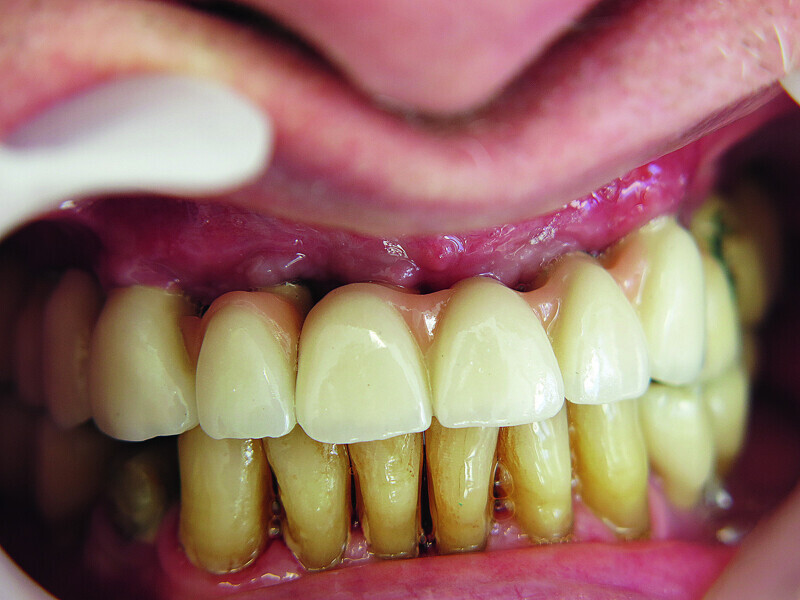

Fig. 12: Screwed on superstructure.